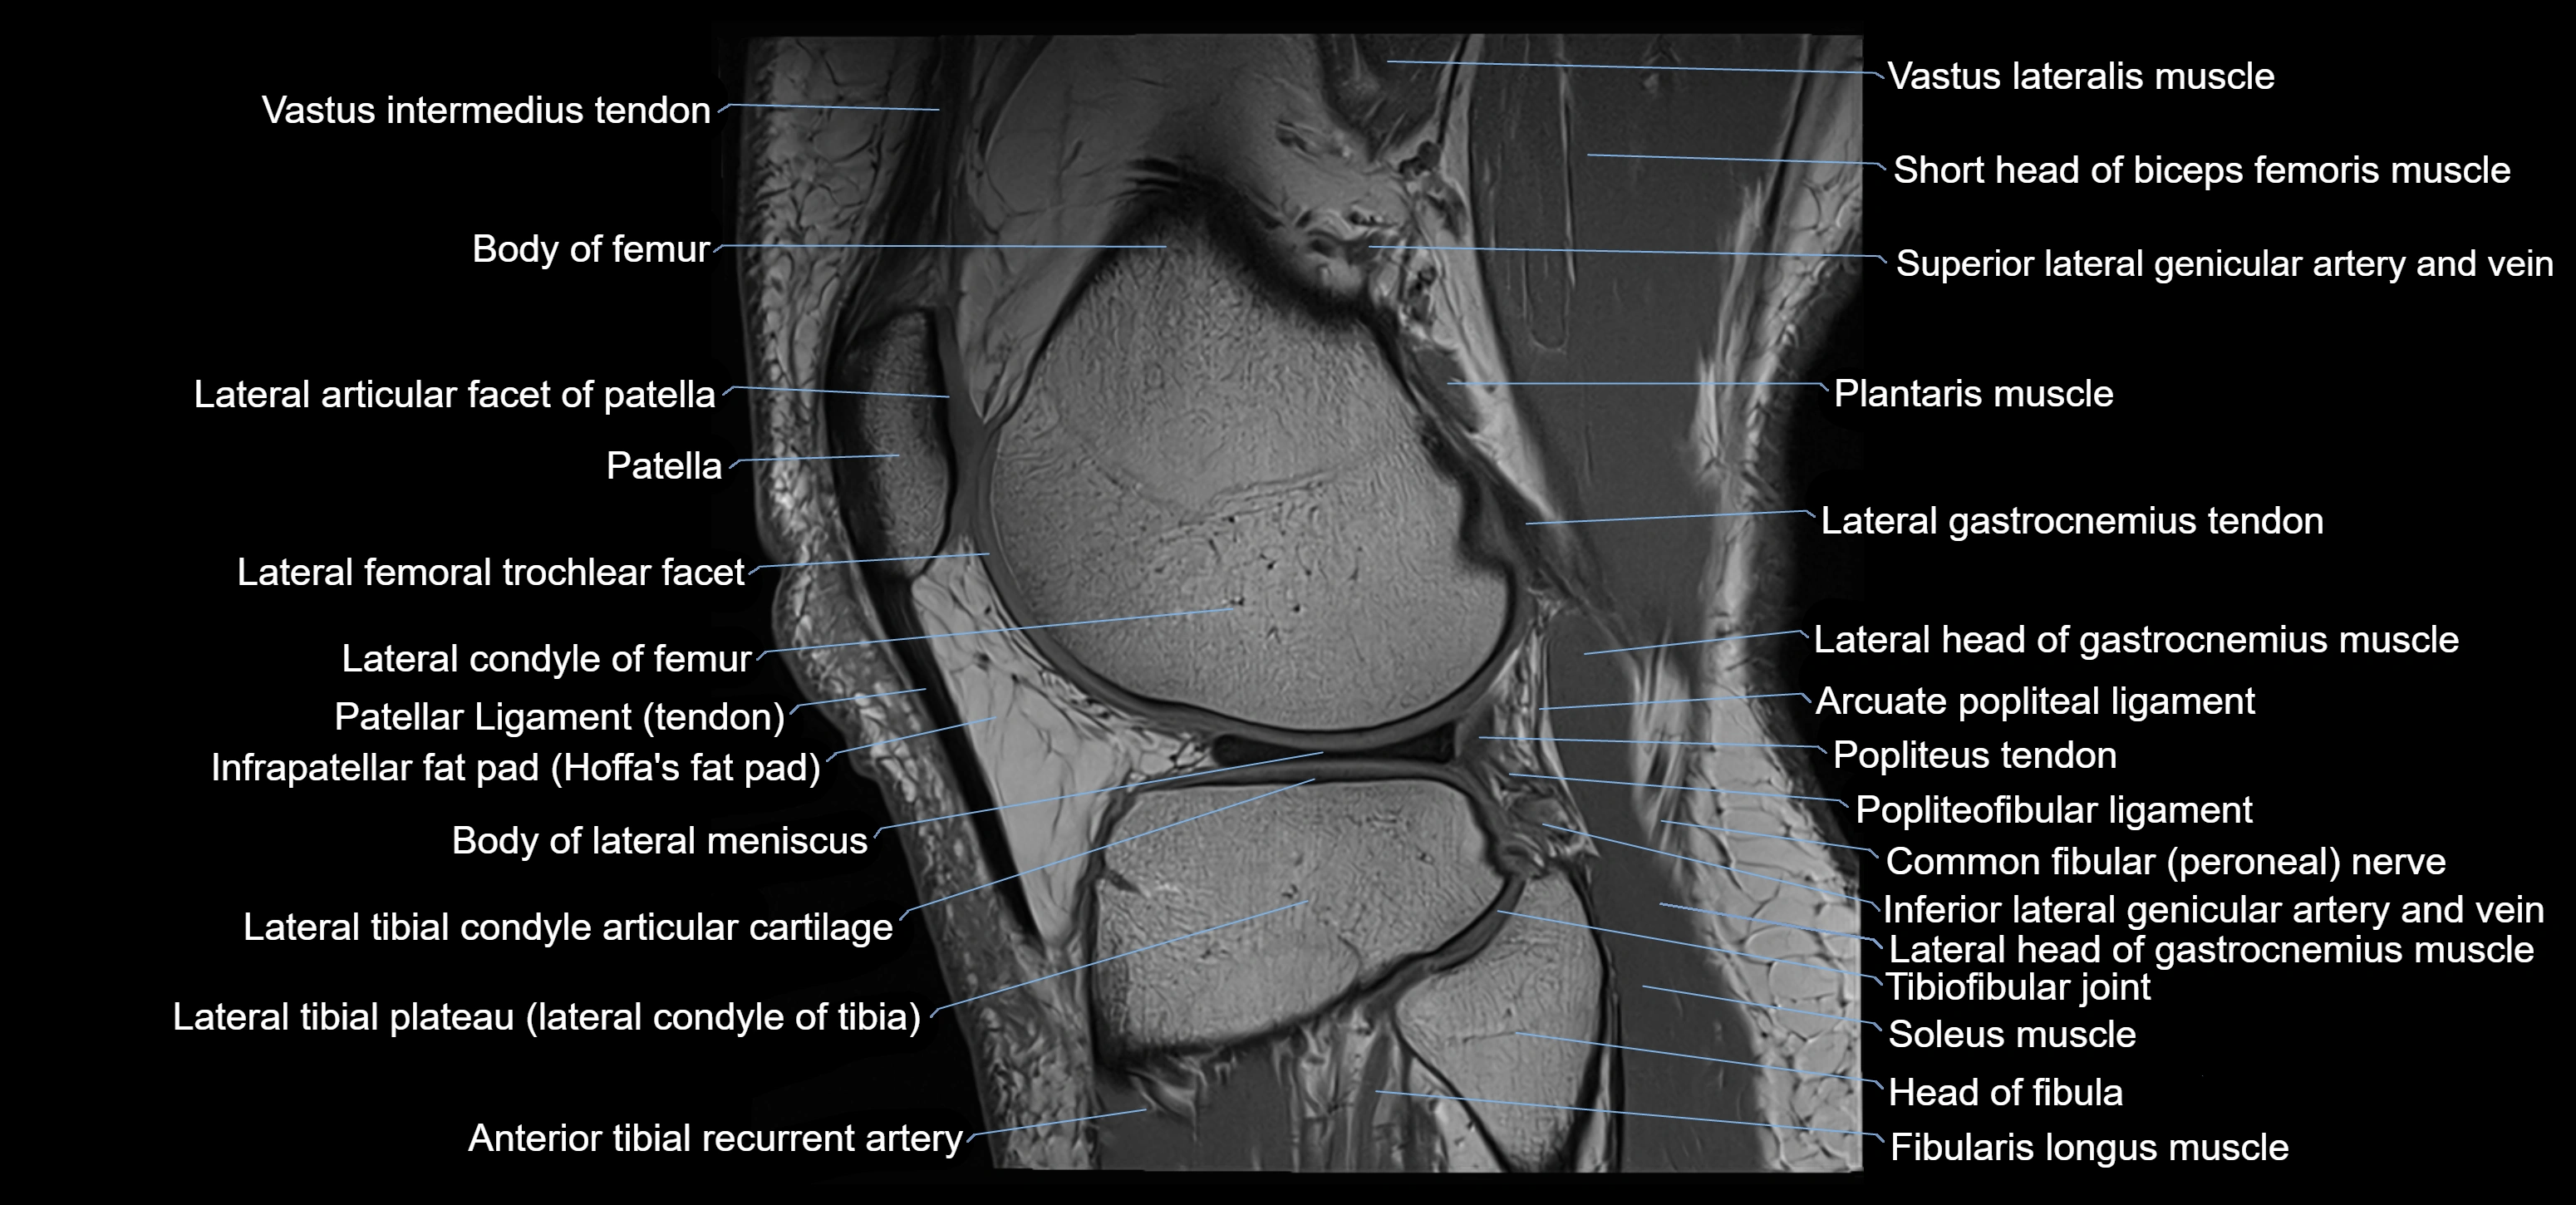

- Arcuate popliteal ligament

- Body of lateral meniscus

- Fibularis longus muscle (peroneus longus muscle)

- Head of fibula

- Inferior lateral genicular artery

- Inferior lateral genicular vein

- Lateral articular facet of patella

- Lateral condyle of femur

- Lateral gastrocnemius tendon

- Lateral head of gastrocnemius muscle

- Lateral meniscus

- Lateral tibial plateau

- Neck of fibula

- Patellar tendon (patellar ligament)

- Plantaris muscle

- Popliteal artery

- Popliteus tendon

- Soleus muscle

- Superior tibiofibular joint

- Vastus lateralis muscle